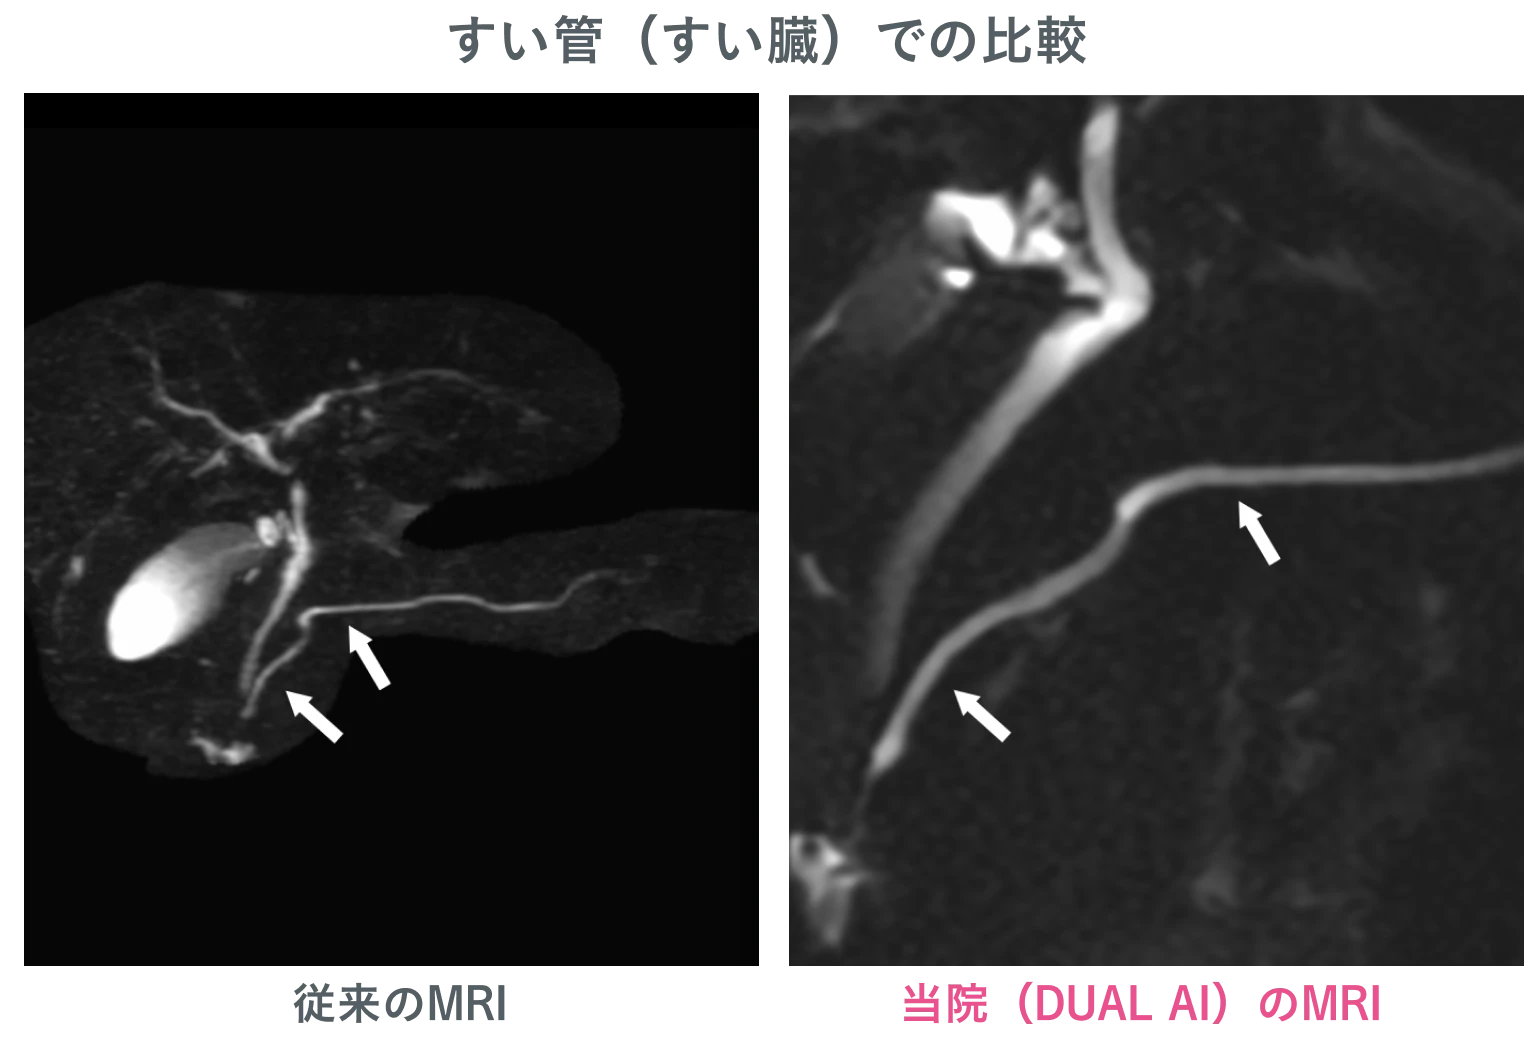

AI を搭載した最新鋭MRI・CTを導入

医療技術の進化を取り入れ、高精度な検査を実現。AI による画像解析により、見落としのリスクを最小限に抑えます。

高原クリニック イノベーティブスキャンのMRIは、すい臓がんの早期発見において高精度な診断を実現しています。